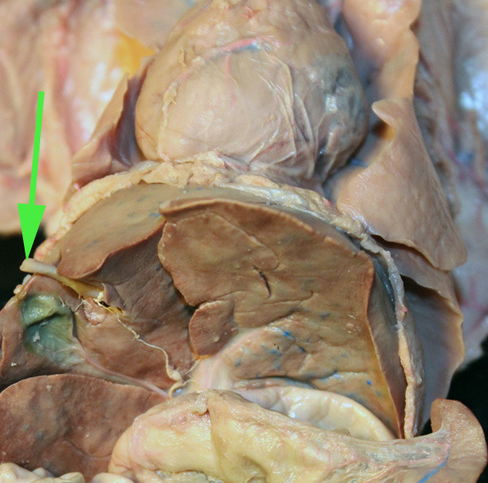

The organ marked by the green arrow is part of the THYMUS gland

The organ marked by the green arrow arrow is the Spleen

The organ indicated by the green arrow is the SPLEEN